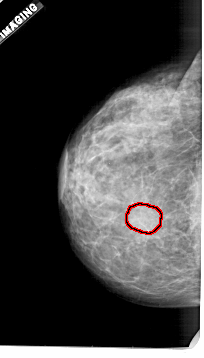

FILE: A_1921_1.LEFT_MLO.OVERLAY

TOTAL_ABNORMALITIES 1

ABNORMALITY 1

LESION_TYPE MASS SHAPE OVAL MARGINS OBSCURED

ASSESSMENT 3

SUBTLETY 2

PATHOLOGY BENIGN

TOTAL_OUTLINES 1

BOUNDARY